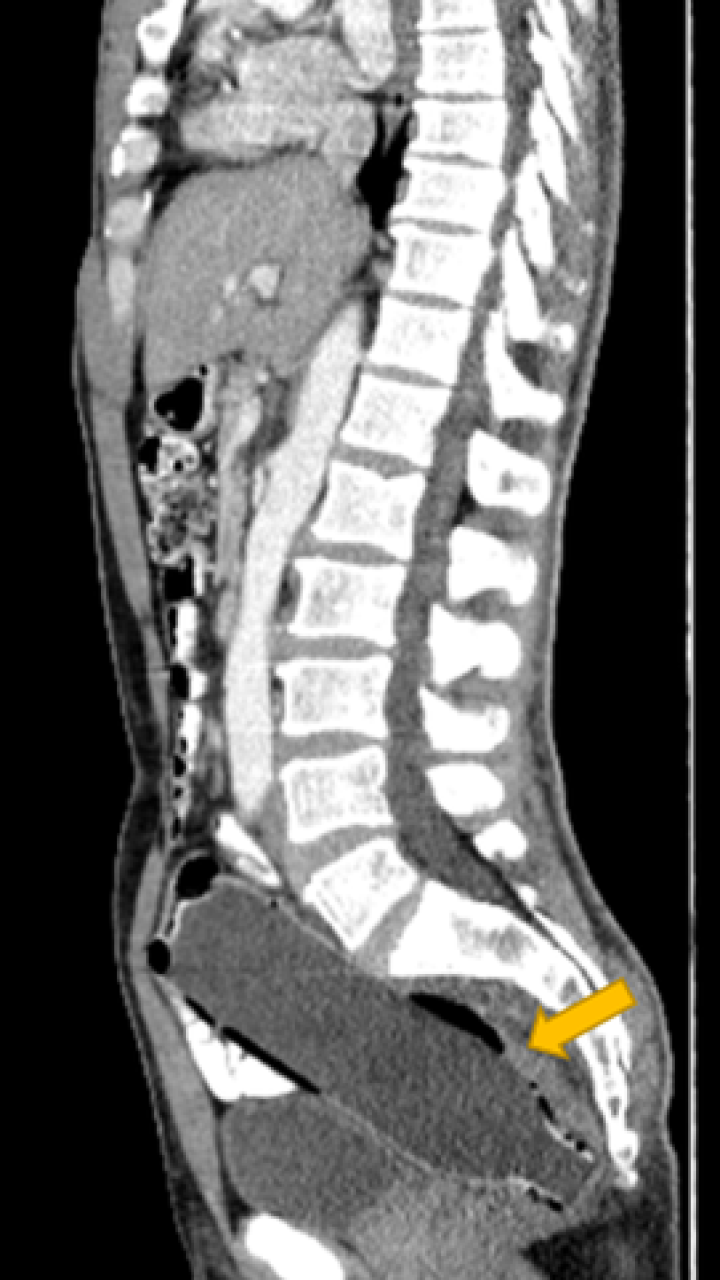

Los médicos le realizaron una tomografía computarizada para ver qué estaba obstruyendo los intestinos del hombre, al paso de unos minutos se percataron de que tenía una botella en su interior.

En la imagen se veía una botella llena de agua de 250 ml

El fondo de la botella estaba ubicado entrando al colon y la tapa a unos 10 mm de la abertura del ano.